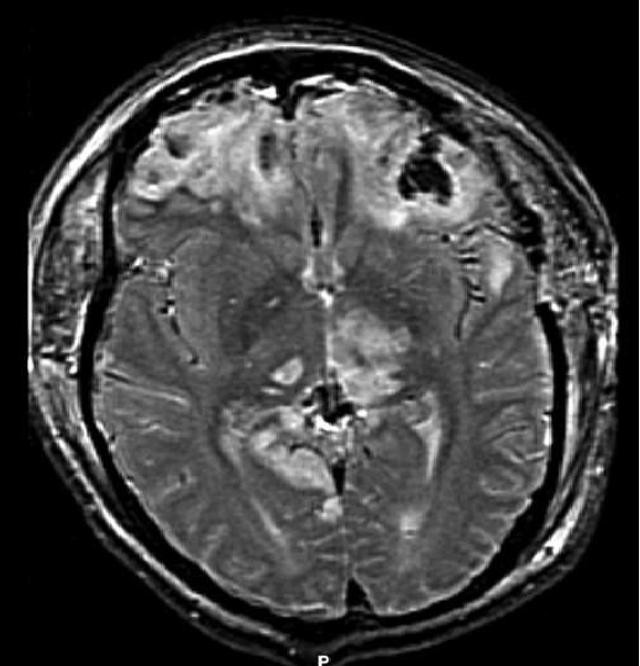

외상성 뇌손상(TBI)의 진단은 병변의 상황과 임상 증거, 특히 신경학적 검사 결과를 바탕으로 의심된다.[162] 신경 영상 검사는 진단 및 예후를 결정하고 적절한 치료법을 결정하는 데 중요한 보조 수단으로 활용된다.[165] 또한, DSM-5는 외상성 뇌손상과 관련된 정신과적 후유증을 진단하는 데 사용될 수 있다.[69][70][71]

신경 영상 검사는 외상성 뇌손상의 진단 및 예후를 결정하고 적절한 치료법을 결정하는 데 도움이 된다.[165]

자기공명영상(MRI)은 CT보다 더 자세한 정보를 보여주며 장기적인 예후에 대한 정보를 추가할 수 있다.[162] 특히 확산성 축삭 손상과 같은 손상 특징을 감지하는 데 CT보다 유용하다.[193] 하지만 MRI는 응급 상황에서는 출혈 및 골절 감지의 상대적 비효율성, 영상 획득 시간이 길다는 점, 기계 내 환자의 접근성 문제, 응급 치료에 사용되는 금속 물체와의 비호환성 등의 이유로 잘 사용되지 않는다.[162] 2012년 이후 MRI의 변형 기술로 고해상도 섬유 추적(HDFT)이 있다.[72]